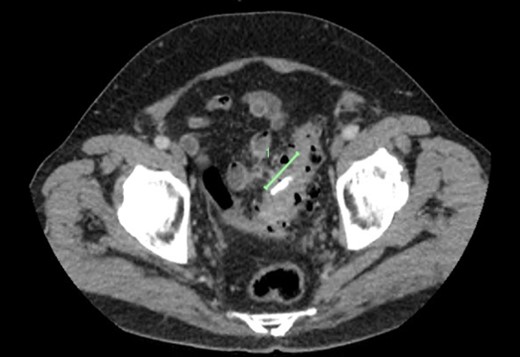

The patient had an outpatient intravenous contrast-enhanced CT abdomen and pelvis (Fig. 1) which demonstrated extensive sigmoid diverticulosis, with diffuse mural thickening and surrounding inflammatory stranding. The surrounding inflammatory changes extended towards a loop of adjacent small bowel. Within the sigmoid lumen at the site of these changes, was noted to be a linear dense foreign body.

CT demonstrating a radio-opaque foreign body (marked) in segment of sigmoid diverticulosis, with stranding extending to adjacent loop of small bowel.